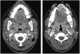

Tonsillitis

Tonsillitis is inflammation of the tonsils in the upper part of the throat. Tonsillitis is a type of pharyngitis that typically comes on fast (rapid onset). [Source: Wikipedia ]